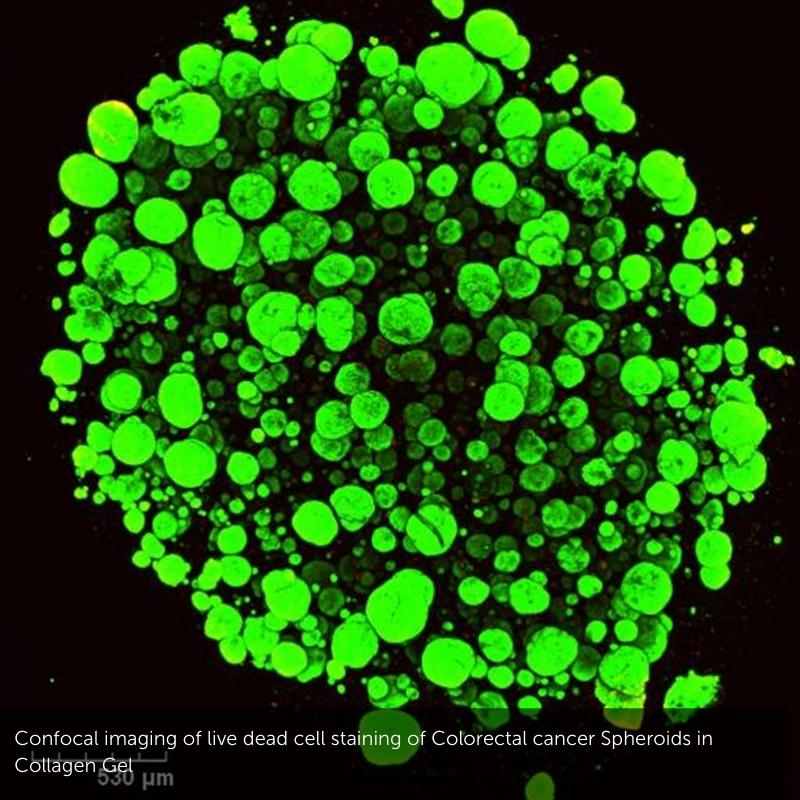

(3) Development of 3D models of the Colorectal Tumour Microenvironment (Funded by Lifetime CDT Programme)

Although there have been many advances in recent years for the treatment of colorectal cancer (CRC), it still remains the third most common cause of cancer-related deaths worldwide. Many patients with late stage CRC display resistance to multiple different therapeutics. An important aspect in developing effective therapeutics for CRC patients is understanding the interactions that take place in the tumour microenvironment (TME), as it has been shown to contribute to immune suppression and drug resistance in vivo. Using approaches such as the GelMA 3D platform, as well as dynamic microfluidic devices, we aim determine the influence of stromal cell interactions on CRC spheroid growth, as well as effects on infiltrating immune cells. We access patient samples to identify immunosuppressive features in the tumour microenvironment; and then use these features to inform the development of 3D multi-cell models to investigate novel ways to improve immune cell activation. We aim to assess how different 3D models may be optimised to study cellular and extracellular interactions that take place in the TME of CRC in an effort to allow the development of more translatable effective treatment options for patients.